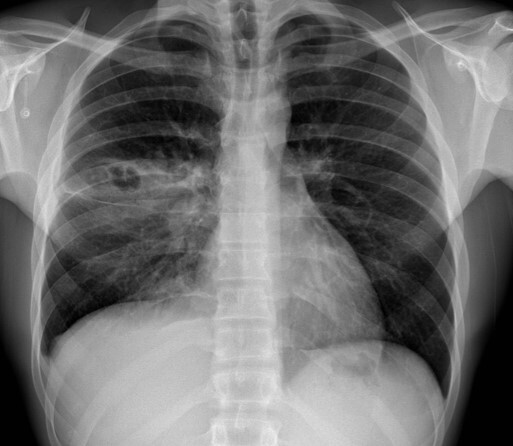

A

RUL and RML pneumonia (multi lobar)